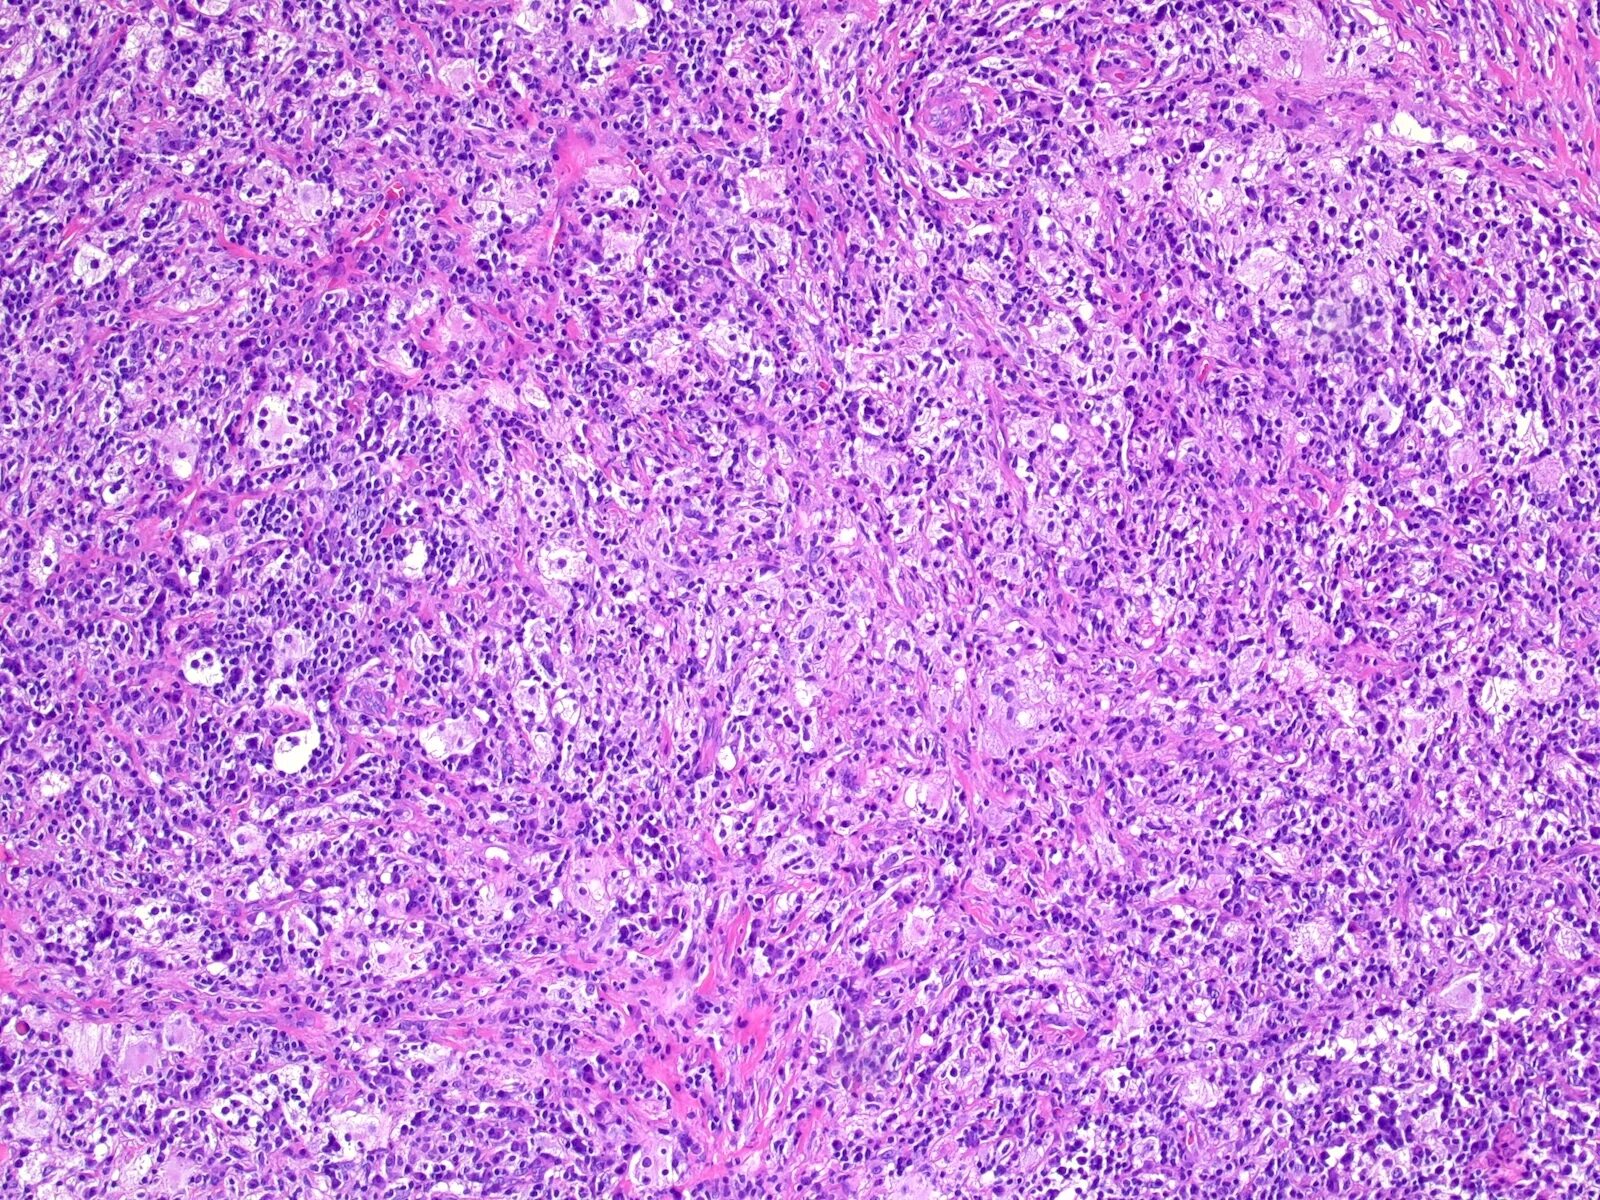

Боюсь гистологии